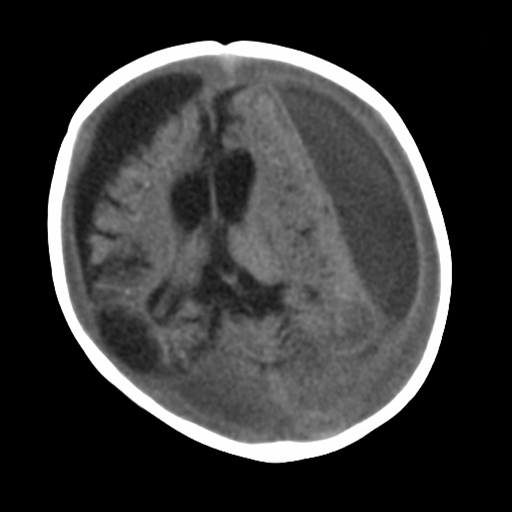

MRI depicting subdural hygromas surrounding severe brain atrophy from abusive head trauma. This child was initially erroneously diagnosed with meningitis

From the personal collection of Alice Newton, MD; used with permission